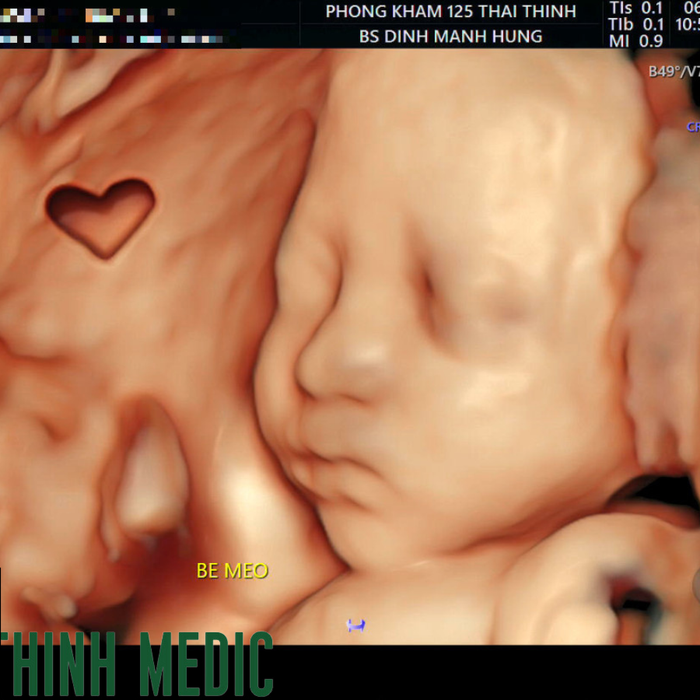

8. Phòng khám Đa khoa 125 Thái Thịnh

Phòng khám Đa khoa 125 Thái Thịnh đã được thành lập và hoạt động từ tháng 10 năm 1998, với hơn 20 năm phục vụ cộng đồng. Đây là phòng khám đa khoa tư nhân được nhiều mẹ bầu tin tưởng nhờ dịch vụ khám và siêu âm thai chất lượng cao, an toàn và hiệu quả.

Phòng khám được trang bị hệ thống thiết bị hiện đại và đầy đủ cho việc thăm khám thai kỳ, bao gồm máy siêu âm 2D, 4D thế hệ mới nhất từ Hoa Kỳ (siêu âm qua bụng và đầu dò âm đạo), máy laser, máy soi tử cung...

Phòng khám đáp ứng đầy đủ nhu cầu khám thai như khám định kỳ, phát hiện dị tật thai nhi và thai nghén nguy cơ cao. Ngoài ra, phòng khám còn cung cấp xét nghiệm sàng lọc không xâm lấn NIPT với các gói từ cơ bản đến nâng cao, sàng lọc 22 cặp NST thường và 1 cặp NST giới tính, hỗ trợ theo dõi và phát hiện các vấn đề sức khỏe của thai nhi.

Khoa phụ sản tại Phòng khám Đa khoa 125 Thái Thịnh quy tụ đội ngũ bác sĩ sản khoa có kinh nghiệm và chuyên môn cao. Để tiện lợi cho khách hàng, phòng khám có hệ thống đặt lịch hẹn qua hotline, website và fanpage. Mẹ bầu nên chủ động đặt lịch hẹn trước để quá trình thăm khám được nhanh chóng và thuận tiện.